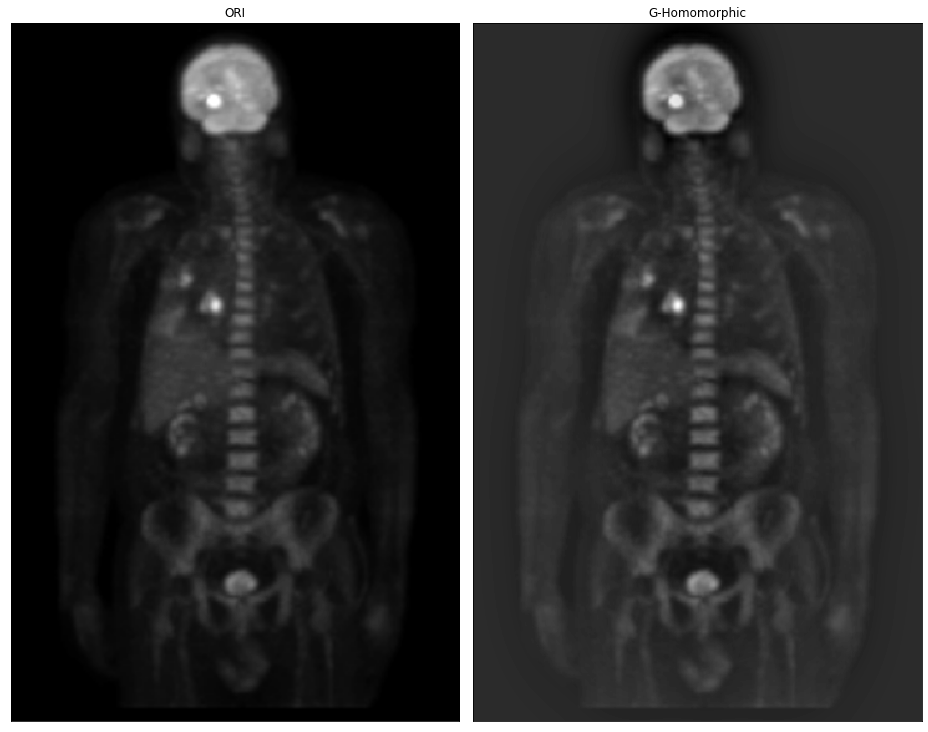

# 高斯同态滤波器

img_ori = cv2.imread('DIP_Figures/DIP3E_Original_Images_CH04/Fig0462(a)(PET_image).tif', -1)

M, N = img_ori.shape[:2]# 填充

fp = pad_image(img_ori, mode='constant')

fp_cen = centralized_2d(fp)

fft = np.fft.fft2(fp_cen)# 滤波器

GHF = gauss_homomorphic_filter(fp, fp.shape, rl=0.5, rh=3, c=5, radius=20)# 滤波后的图像

img_new = frequency_filter(fft, GHF)

img_new = img_new[:M, :N]

# print(img_new.min(), img_new.max())

img_res = np.uint8(normalize((img_new)) * 255)plt.figure(figsize=(13, 14))

plt.subplot(1, 2, 1), plt.imshow(img_ori,'gray'),plt.title('ORI'), plt.xticks([]), plt.yticks([])

plt.subplot(1, 2, 2), plt.imshow(img_res,'gray'),plt.title('G-Homomorphic'), plt.xticks([]), plt.yticks([])

plt.tight_layout()

plt.show()